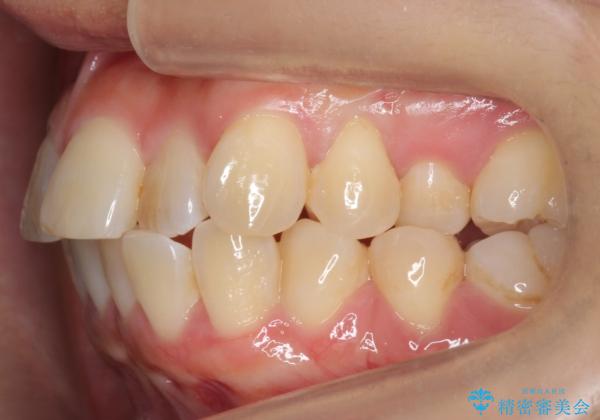

- 前歯の並びを気にして来院。

左上の前歯が内側に入って反対咬合になっていました。

また、左上5番も反対咬合でした。